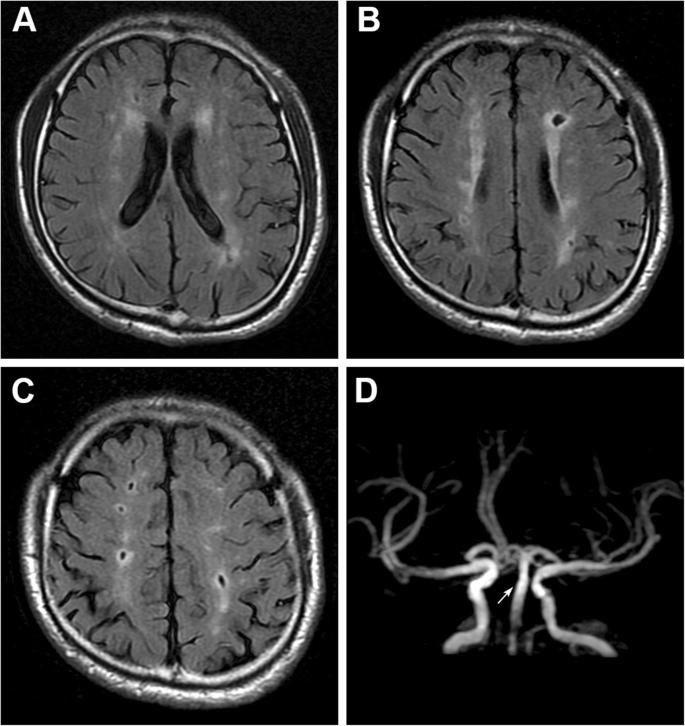

二、无症状的腔梗。

如果出现腔隙性脑梗死该怎么办呢?

当然,这个问题其实也应该分情况讨论。

如果有了具体症状,腔梗还是该治疗的,比如一侧肢体的运动感觉障碍,这个时候要谨慎,具体怎么治疗还是听医生的吩咐比较好。

但是如果没什么表现,仅仅是在体检或者在检查其他疾病的过程中发现有腔梗,这个时候该怎么办呢?

临床当中这种情况是很常见的,我们称为无症状的腔隙性脑梗死,对于这类患者,请您别害怕。

虽然我们称之为脑梗死,但他对我们的危害并不大,只需要改善生活方式,积极预防下一次腔梗就可以了。

四、脑白质脱髓鞘。

面对一份头部的CT报告单,最常见的字眼其实就是脑白质脱髓鞘了,对于这种问题该怎么解决呢?

其实对于大多数患者来说,并不需要解决。

看上去脑白,质脱髓鞘是一种疾病,可是实际上只要岁数到了,或多或少都会有这种情况,轻度的脑白质脱髓鞘在55岁以上的人群当中其实是很常见的。

当然,很多人虽然有脑白质脱髓鞘,但并没有什么症状也没有什么感觉。

对于这类患者其实并不需要治疗,症状较轻的时候也没有什么好的治疗方式可以改善,最重要的就是强调改善生活方式,把自己大脑子的状态调整好。

但是要谨慎,如果是非常严重的脑白质脱髓鞘可能就是一种疾病了,我们也应该好好的治疗,比如脑神经炎,而且出现头痛。